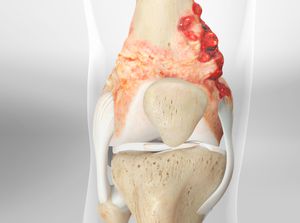

Bone cancer surgery involves the removal of cancerous bone tumors and surrounding tissues to treat bone cancer. This procedure aims to eliminate the tumor while preserving as much healthy bone and surrounding tissue as possible. It is often combined with other treatments like chemotherapy or radiation to enhance effectiveness and prevent recurrence.

• Localized Tumors: When bone cancer is localized and the tumor can be removed surgically to prevent it from spreading or worsening.

Directly removes cancerous tissue, potentially eliminating the source of the cancer and preventing further spread. This targeted approach can halt disease progression and reduce future complications, offering a definitive solution to localized cancer.